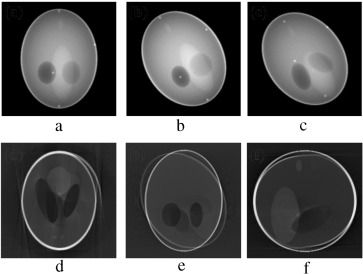

(a–c) Axial, coronal and sagittal slices of the gradual pitch motion corrupted ...

Figure 15.

(a–c) Axial, coronal and sagittal slices of the gradual pitch motion corrupted case. (d–f) Same slices after motion compensation.

(a–c) Axial, coronal and sagittal slices of the gradual roll motion corrupted ...

Figure 16.

(a–c) Axial, coronal and sagittal slices of the gradual roll motion corrupted case. (d–f) Same slices after motion compensation.

In the second stage of verification, the performance of our proposed marker-based estimator is tested with all the abrupt motion-corrupted cases of Figure 7 , Figure 8  and Figure 9 . Simulation results of actual and estimated motion parameters are listed in Table 6 , Table 7  and Table 8 . Estimated translation motion parameters are within 1.5% of actual values, and estimated rotational parameters are within 0.1% of actual values. Now, to demonstrate the efficacy of our proposed artifact mitigation technique, we apply the estimated motion parameters to the back-projection stage of the MB_FDK algorithm to reconstruct the 3D volume from the above different cases of motion corrupted projection data sets. In Figure 14 , Figure 15  and Figure 16 , we plotted the axial, coronal and sagittal slices taken from the reconstructed volume of different gradual rotational motion corrupted cases and motion artifacts compensated cases, side by side. From these figures, it can be observed that the motion artifacts originated from the gradual variations of motion have significantly been reduced by the MB_FDK approach. In Figure 17 , Figure 18  and Figure 19 , we plotted the axial, coronal and sagittal slices taken from the reconstructed volume of abrupt motion corrupted cases and motion artifacts compensated cases, side by side. From these plots it can also be inferred that the MB_FDK approach has significantly reduced the motion artifacts originated from the abrupt and large variations of motion.